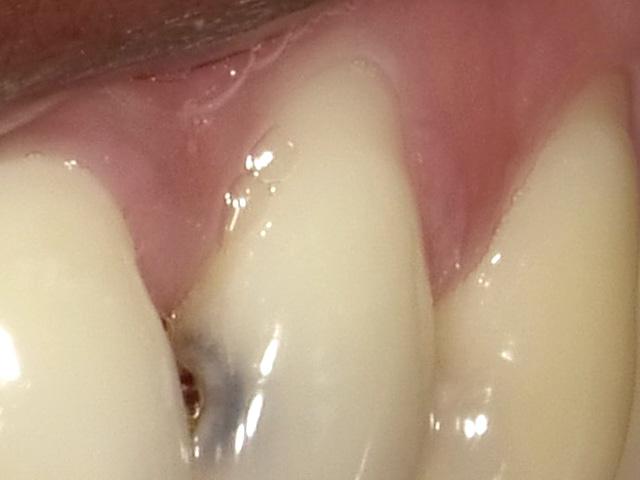

Remarkably, the patient’s chief concern was the gingival recession on the left maxillary lateral, not the mesial caries. (Fig. 8) Fortunately, the patient’s oral hygiene was relatively good, and restoring the MLB decay was

straightforward (BeautiBond (Fig. 7) and Beautifil Flow Plus X, both from Shofu USA, San Marcos CA). The steps for the esthetic rectification of the buccal recession are: